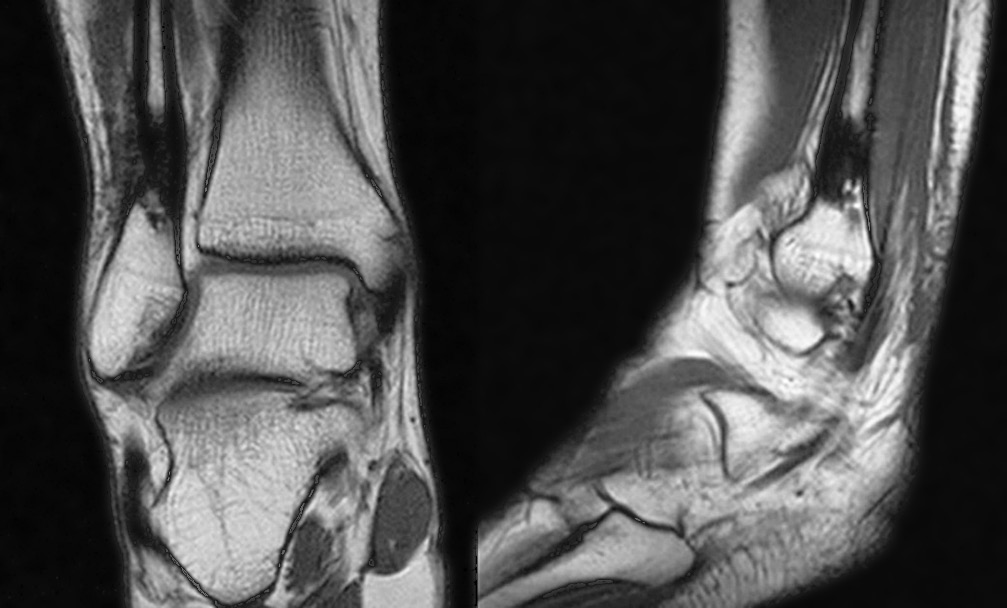

В послеоперационном периоде выраженность болевого синдрома снизилась (до 4–6 баллов по ВАШ). Проводили интенсивные реабилитационные мероприятия. Спустя 4 мес. после резекции склерозированного участка нижней трети малоберцовой кости на контрольной рентгенограмме определялись неоднородность структуры и нечеткость контуров дистального метадиафиза малоберцовой кости с формированием костной мозоли (рис. 6). Признана целесообразной полная нагрузка на конечность. При осмотре через 6 мес. после операции болевой синдром отсутствовал (по ВАШ 0 баллов), наблюдалась потеря чувствительности в области тыльной поверхности стопы. Последующее обследование через 12 мес. после резекции показало отсутствие болевого синдрома и других клинических проявлений. По данным компьютерной томографии прослеживалась отчетливая тенденция к восстановлению органотипической костной структуры нижней трети малоберцовой кости в зоне оперативного вмешательства (рис. 7).

Рис. 6. Рентгенограмма спустя 4 мес. после операции (сегментарной резекции). Образование костной мозоли, заполнение дефекта кости новообразованной костной тканью

Рис. 7. Мультиспиральная компьютерная томография спустя 12 мес. после операции — сегментарной резекции нижней трети малоберцовой кости. Определяются признаки наметившейся дифференциации костной структуры на кортикальный слой и костномозговую полость